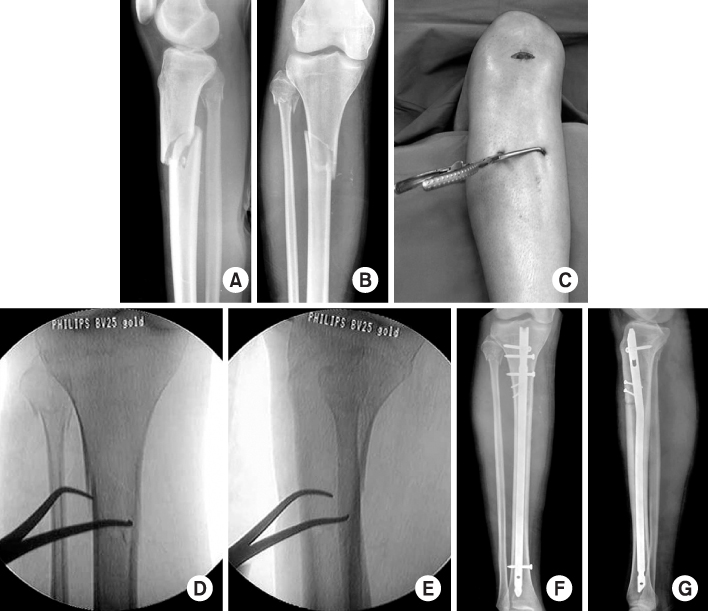

Fig. 1

Radiographs show a healed fracture of the proximal tibia with valgus deformity and apex anterior deformity after locked nail.

(A, B) Initial radiographs show simple oblique fracture of the proximal tibia.

(C, D, E) The fracture was reduced and alignment was maintained by temporary percutaneous use of pointed reduction forceps during nailing procedures.

(F, G) Postoperative radiographs show anatomical reduction of the fracture after fixing with a locked tibial nail and adjunctive percutaneous lag screws.